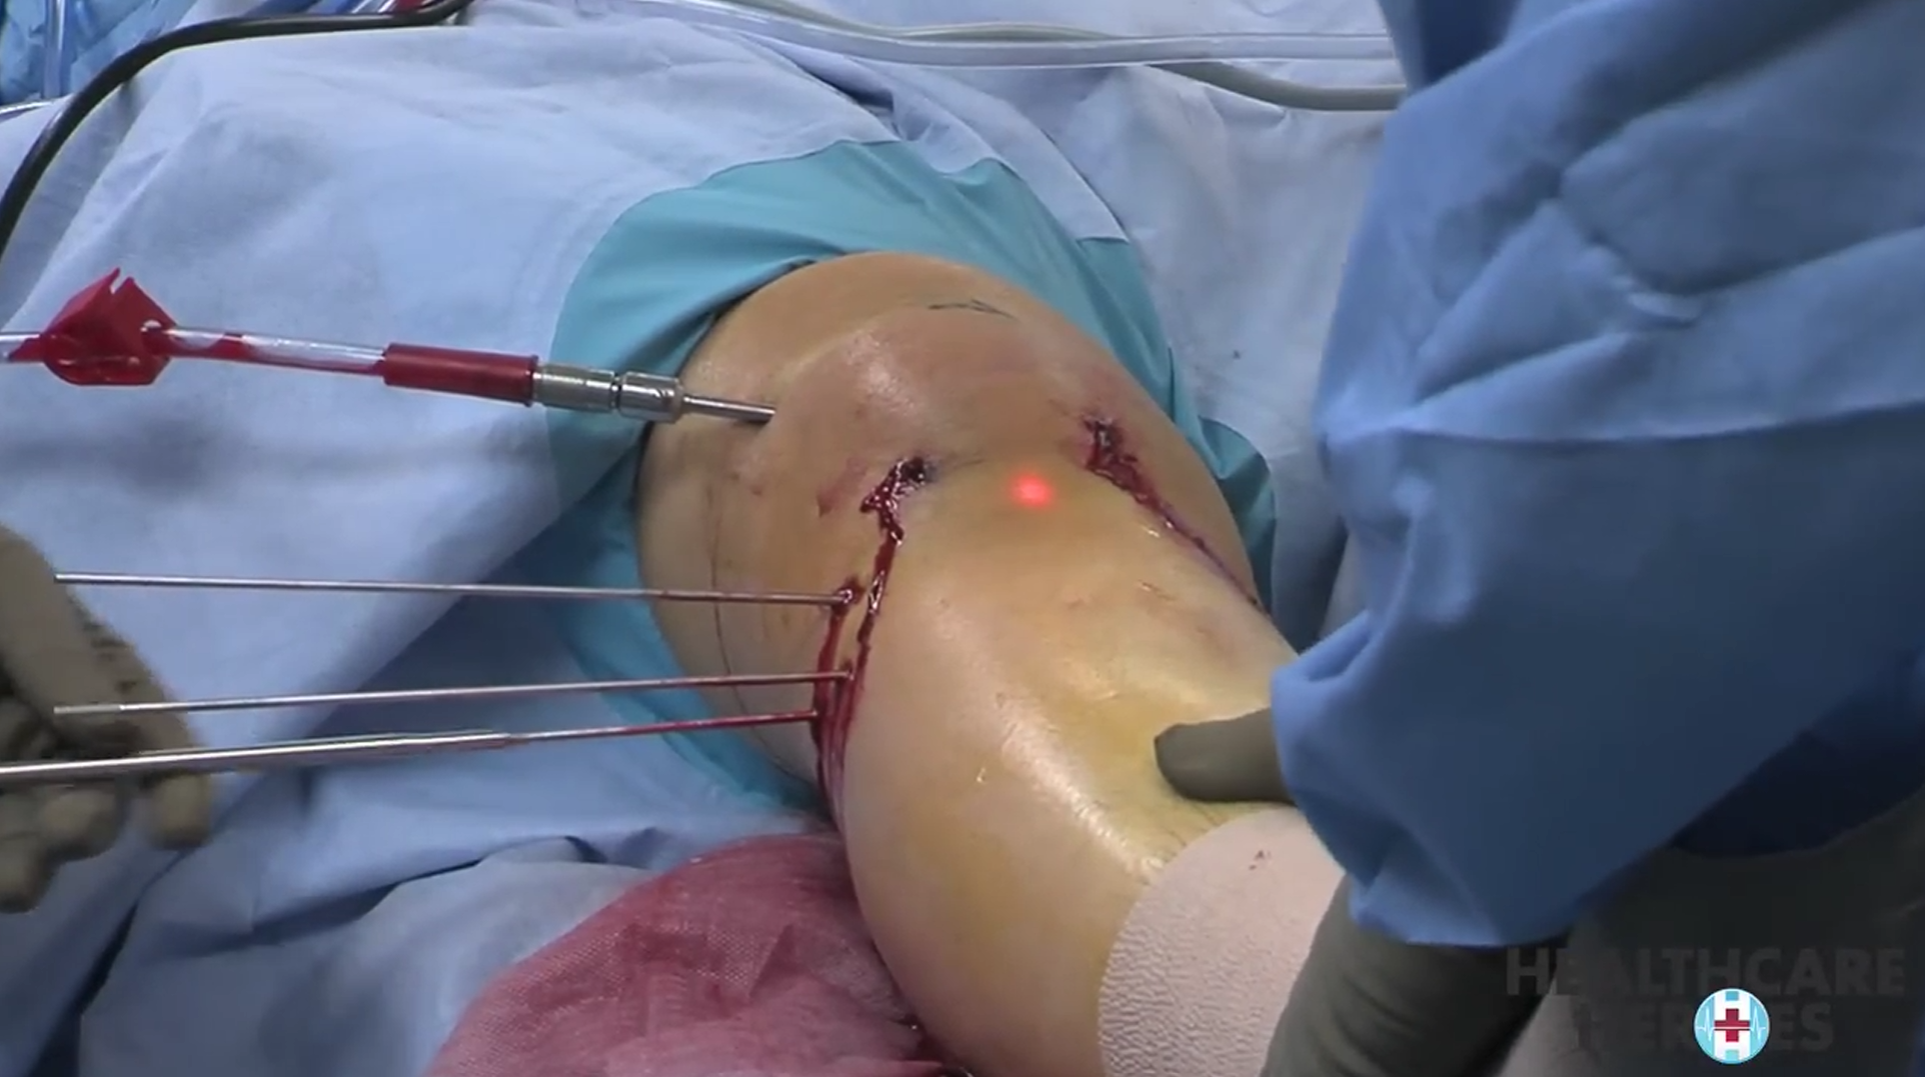

Cilt Grefti Uygulaması

Cilt Grefti Uygulaması

Cilt Grefti Uygulaması